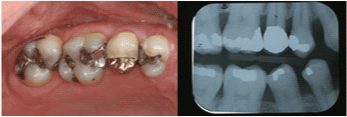

| Mandibular Right Second

Molar |

11 |

43.8% |